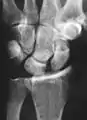

X-ray images indicate scapholunate ligament instability when the scapholunate distance is more than 3 mm, which is called scapholunate dissociation.[7] A static scapholunate instability is generally readily visible, but a dynamic scapholunate instability can only be seen radiographically in certain wrist positions or under certain loading conditions, such as when clenching the wrist, or loading the wrist in ulnar deviation.[6]

In order to diagnose a SLAC wrist you need a posterior anterior (PA) view X-ray, a lateral view X-ray and a fist view X-ray.[8] The fist X-ray is often made if there is no convincing Terry Thomas sign. A fist X-ray of a scapholunate ligament rupture will show a descending capitate bone. Making a fist will give pressure at the capitate, which will descend if there is a rupture in the scapholunate ligament.